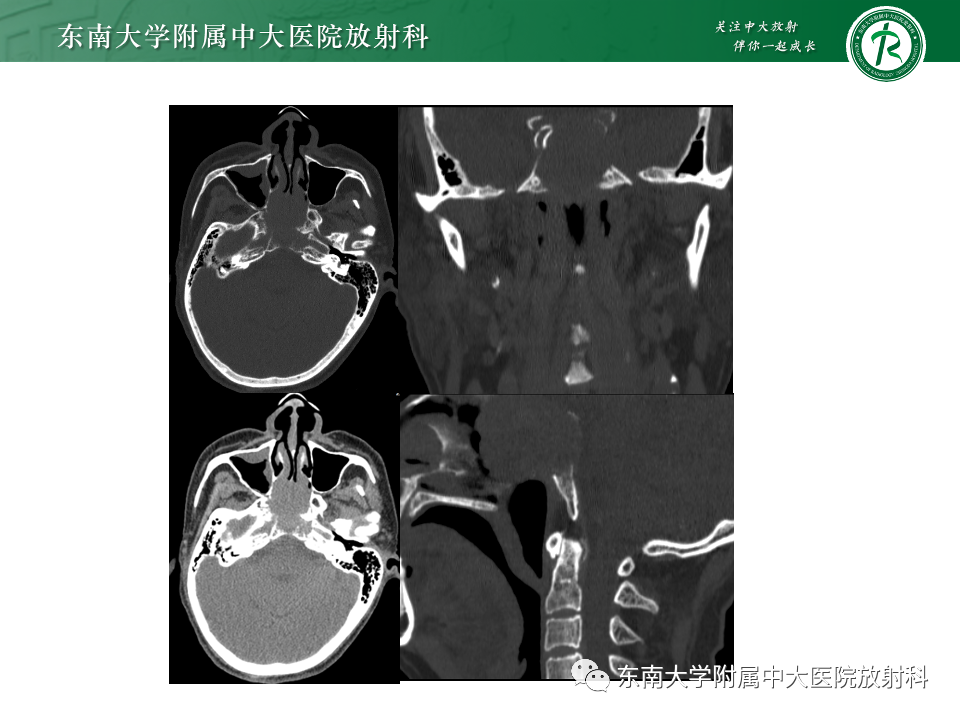

病例1:脊索瘤

病例2:弥漫大B细胞淋巴瘤

病例3:侵袭性垂体瘤

病例4:鼻咽癌